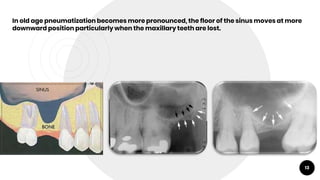

In old age pneumatization becomes more pronounced, the floor of the sinus moves at more

downward position particularly when the maxillary teeth are lost.